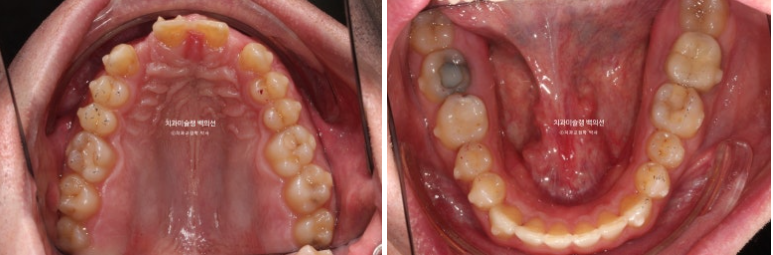

오늘은 부원장님 인비절라인 케이스를 보면서 앞니 2개가 선천적으로 없는 경우 (결손치) 인비절라인 교정 후 임플란트까지 치료 진행과정에 대해 보여드리겠습니다.

24년 1월 교정치료를 위해 내원한 외국인 환자분입니다.

23.01

위 앞니 4개중 2개가 없습니다. 앞니가 크게 벌어져 있고 아래 앞니가 위로 솟아 위 입천장 잇몸을 칠 정도의 심한 과개교합이 있습니다.